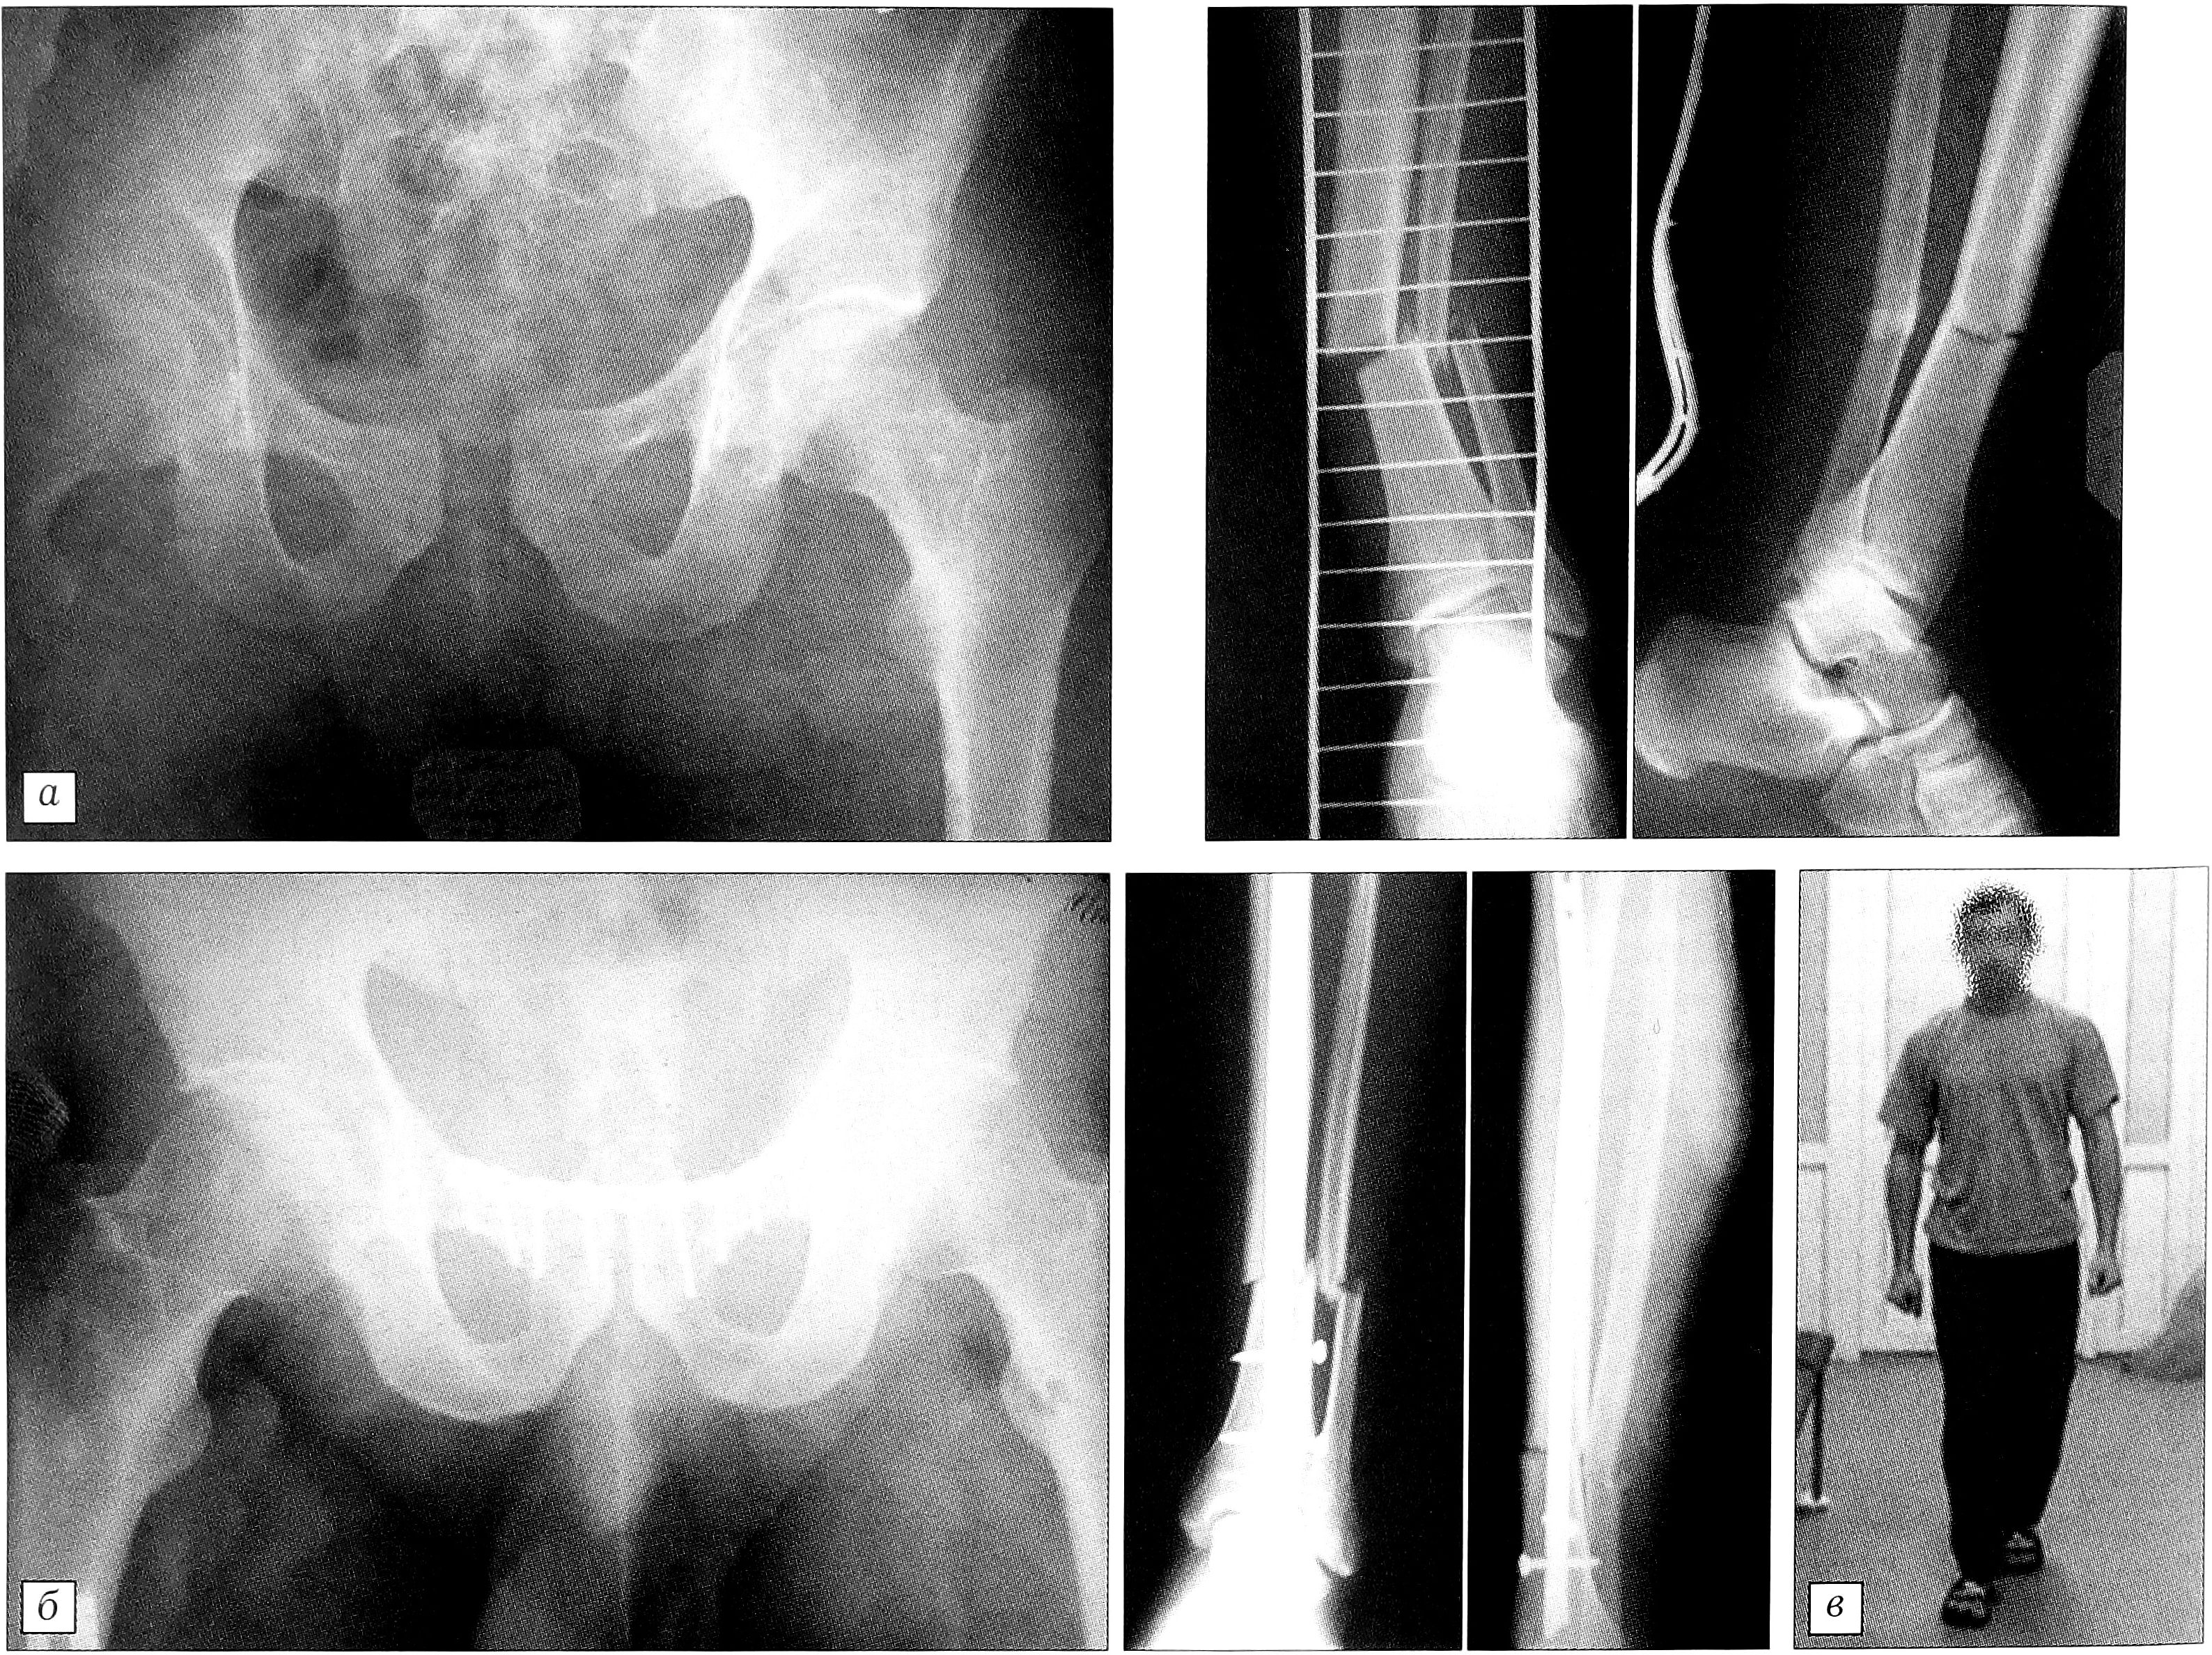

Пример. Больной Р.,26 лет, в результате ДТП получил разрыв симфиза и перелом костей левой голени в нижней трети (рис. 4, а). Через 5 дней после травмы произведены одновременно остеосинтез переднего полукольца таза реконструктивной пластиной АО и интрамедуллярный остеосинтез левой большеберцовой кости стержнем UTN без рассверливания костномозгового канала (рис. 4, б). Уже через неделю после операции больной мог самостоятельно ходить даже без дополнительных средств опоры (рис. 4, в).

Рис. 4. Больной Р. Диагноз: разрыв симфиза, перелом костей левой голени в нижней трети. а — рентгенограммы при поступлении; б — после остеосинтеза; в — функциональные возможности через 1 нед после операции.